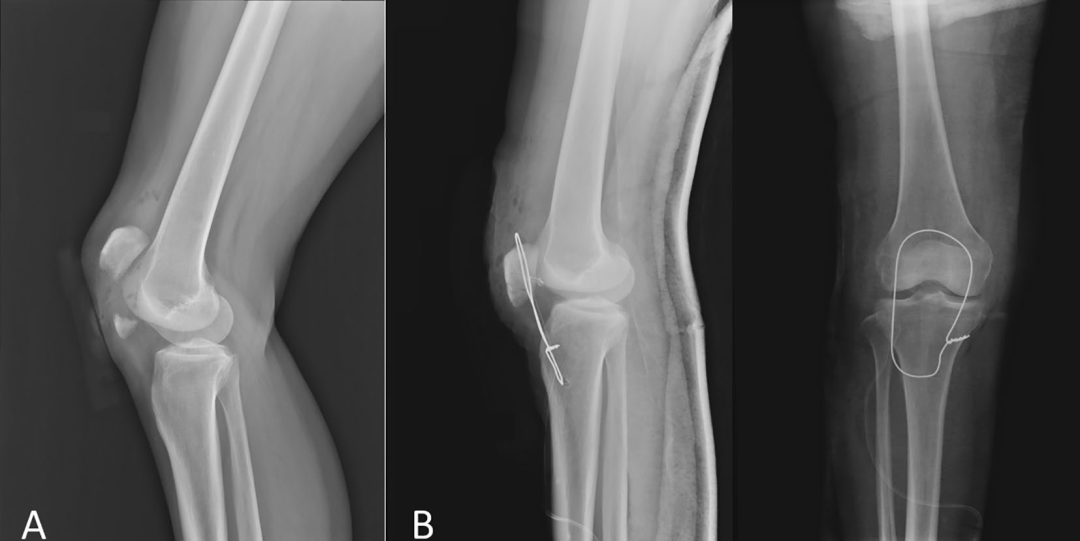

图4. 对照组和实验组患者术后骨折愈合情况比较a-d。患者男,42岁,入院前4 h因跌倒致骨折入院。

a.术前x线侧位片

b.术后x线侧位片

c.术后12周随访x线侧位片。患者女,38岁,入院前3 h因跌倒致骨折入院

d.术前矢状面CT检查

e.术后x线侧位片

f.术后12周随访x线侧位片

髌骨下极骨折可以通过生成的骨孔进行简单的钢丝环扎术轻松复位。然而,需要特别注意避免剥离骨折周围多余的软组织,以防止粉碎性骨块移位和增加复位难度。与单独使用髌骨聚合器相比,钢丝环扎联合髌骨聚合器复位髌骨下极骨折更满意,固定可靠,早期功能锻炼,骨折愈合快。